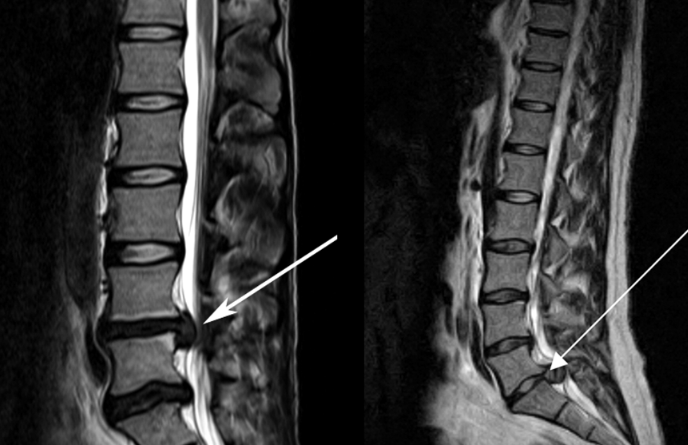

![]() 關(guān)于腰椎間盤突出 ![]() 腰椎間盤突出癥是纖維環(huán)破裂后髓核突出壓迫神經(jīng)根造成以腰腿痛為主要表現(xiàn)的疾病。腰椎間盤退行性改變或外傷所致纖維環(huán)破裂,髓核從破裂處脫出,壓迫腰椎神經(jīng),從而出現(xiàn)腰腿放射性疼痛。 ![]() 病因: 一、退行性變: 目前認(rèn)為,其基本病因是腰椎間盤的退行性變。退行性變是一切生物生、長、衰、亡的客觀規(guī)律,由于腰椎所承擔(dān)的特殊的生理功能,腰椎間盤的退行性變比 其他組織器官要早,而且進(jìn)展相對要快。這個過程是一個長期,復(fù)雜的過程。所謂腰椎間盤退行性改變:即由于椎間盤受體重的壓迫,加上腰部又經(jīng)常進(jìn)行彎曲、后伸等活動,易造成椎間盤的擠壓和磨損,尤其是下腰部的椎間盤,從而產(chǎn)生退行性改變。腰椎間盤退行性改變是本病發(fā)生的基礎(chǔ)?!?/p> 二、其他因素: 1、外力作用:在日常生活和工作中,部分人往往存在長期腰部用力不當(dāng)、過度用力姿勢或體位的不正確等情況。例如長期從事彎腰工作的煤礦工人和建筑工人需經(jīng)常彎腰提舉重物。這些長期反復(fù)的外力造成的損傷日積月累地作用于椎間盤,加重了退變的程度。 2、椎間盤自身解剖因素的弱點(diǎn): (1) 椎間盤在成人之后逐漸缺乏血液循環(huán),修復(fù)能力也較差,特別是在退變產(chǎn)生后,修復(fù)能力更加微弱。 (2) 椎間盤后外側(cè)的纖維環(huán)較為薄弱,而后縱韌帶在腰5、骶1平面時寬度顯著減少,對纖維環(huán)的加強(qiáng)作用明顯減弱。 (3) 腰骶段先天異常:腰骶段畸形可使發(fā)病率增高,這些異常造成椎間隙寬度不等,并常造成關(guān)節(jié)突出,關(guān)節(jié)受到更多的旋轉(zhuǎn)勞損,使纖維環(huán)受到的壓力不一,加速退變。 3、種族、遺傳因素:有色人種發(fā)病率較低,例如印第安人和非洲黑人等發(fā)病率較其他民族明顯要低。 ![]() 2 病理 腰椎間盤突出癥的病理變化過程大致可分為三個階段: 1、突出前期:髓核因退變和損傷可變成碎塊狀物,或呈瘢痕樣結(jié)締組織,變性的纖維環(huán)可因反復(fù)損傷而變薄變軟或產(chǎn)生裂隙。此期病人可有腰部不適或疼痛,但無放射性下肢痛。也有的人原無病變,可因一次大的暴力引起髓核突出。 2、突出期:外傷或正常的活動使椎間盤壓力增加時,髓核從纖維環(huán)薄弱處或破裂處突出。突出物刺激或壓迫神經(jīng)根即發(fā)生放射性下肢痛,或壓迫馬尾神經(jīng)發(fā)生大小便功能障礙。在老 年患者,可因椎間盤退變,整個纖維環(huán)變得軟弱松弛,椎間盤可呈彌漫性向周圍膨出。 3、突出晚期:腰椎間盤突出后,病程較長者,椎間盤本身和其他鄰近結(jié)構(gòu)均可發(fā)生各種繼發(fā)性病理改變。 3 誘發(fā)因素 腰椎間盤突出癥的基本因素是椎間盤退變,但某些誘發(fā)因素可致使椎間隙壓力增高,引起髓核突出。此種誘發(fā)因素常與以下因素有關(guān): 1. 年齡因素:腰椎間盤突出癥的好發(fā)年齡在30-50歲,平均手術(shù)年齡在40歲,因此退變可能是其重要因素。 2. 身高與性別:有人認(rèn)為身材過高也會易發(fā)腰突癥,而男性發(fā)病率是女性的5倍。 3. 增加腹壓:臨床上有約1/3的病人在發(fā)病前有明確的增加腹壓的因素,如劇烈的咳嗽、噴嚏、屏氣、用力排便等。使腹壓增高,破壞了椎節(jié)與椎管之間的平衡狀態(tài)。 4. 不良體位:人在完成各種工作時,需要不斷更換各種體位以緩解腰部壓力,如長期處于某一體位不變,即可導(dǎo)致局部的累積性損傷。特別是長期處于不良姿勢更容易誘發(fā)本病。 5. 職業(yè)因素:重體力勞動者發(fā)病率最高,白領(lǐng)勞動者最低。汽車駕駛員由于長期處于顛簸和振動狀態(tài),椎間盤承受的壓力大且反復(fù)變化,也易誘發(fā)椎間盤突出?!?/p> 6. 受寒受濕:寒冷或潮濕可引起小血管收縮、肌肉痙攣,使椎間盤的壓力增加,可能造成退變的椎間盤破裂。 ![]() ![]() ![]() ![]() 癥狀: 腰椎間盤突出癥患者最多見的癥狀為疼痛,可表現(xiàn)為腰背痛、坐骨神經(jīng)痛,典型的坐骨神經(jīng)痛表現(xiàn)為由臀部、大腿后側(cè)、小腿外側(cè)至跟部或足背的放射痛。據(jù)臨床統(tǒng)計,約95%的腰突癥患者有不同程度的腰痛,80%的患者有下肢痛。特別是腰痛,不僅是腰椎間盤突出最常見的癥狀,也是最早出現(xiàn)的癥狀之一。 ![]() ![]() ![]() 檢查: 1、X線:腰椎間盤所包括的髓核、纖維環(huán)和軟骨板密度均較低,在X線下并不顯影,因此臨床上腰突癥患者的腰椎X線平片可僅有一些非特異性的變化,甚至無異常變化。因此單純腰椎平片并不能作為有無腰椎間盤突出癥的直接依據(jù),但X線能發(fā)現(xiàn)腰椎的退行性改變和結(jié)構(gòu)異常,對提示椎間盤的退變有重要意義,并且能排除其他的一些腰椎疾患,如腰椎結(jié)核、腫瘤和腰椎滑脫等。典型的腰椎間盤突出癥患者通過病史、體征和X線平片即能作出初步的診斷。 2、CT檢查:腰椎的CT可以清楚地顯示椎間盤突出的部位、大小、形態(tài)和神經(jīng)根、硬脊膜受壓的情況,同時還可顯示黃韌帶肥厚、小關(guān)節(jié)增生、椎管和側(cè)隱窩狹窄等情況。對腰椎間盤突出癥診斷的準(zhǔn)確率達(dá)到80%-92%?!?/p> 3、核磁共振(MRI):核磁共振沒有輻射,可以多方位成像(橫斷面、冠狀面、矢狀面和斜面),對解剖細(xì)節(jié)顯示較好,對組織結(jié)構(gòu)的細(xì)微病理變化更敏感(如骨髓的浸潤),可以排除神經(jīng)和脊柱腫瘤等。對于一些落到椎管的髓核組織也不會遺漏?!?/p> 4、脊髓造影:脊髓造影利用椎管內(nèi)蛛網(wǎng)膜下腔的空隙,注入造影劑后在X線下攝片,顯示椎管內(nèi)部結(jié)構(gòu)。目前常用水溶性造影劑,能較清晰地顯示硬膜腔、馬尾神經(jīng)和神經(jīng)根鞘,對腰椎間盤突出癥的診斷可達(dá)90%左右,主要X線表現(xiàn)為硬膜囊壓迫征象和神經(jīng)根鞘壓迫征象。但由于CT和MRI在臨床的廣泛應(yīng)用,無創(chuàng)傷且診斷率更高,脊髓造影在臨床上的應(yīng)用已經(jīng)大大減少,而且由于它副作用較大,甚至可能造成截癱等嚴(yán)重情況,目前主張慎重選用?!?/p> 5、肌電圖:肌電圖是對周圍神經(jīng)與肌肉的電生理檢查方法,可用于觀察并記錄肌肉在靜止、主動收縮和支配其的周圍神經(jīng)受刺激時的電活動,同時也可用來測量周圍神經(jīng)的傳導(dǎo)速度。在腰椎間盤突出癥上,肌電圖主要通過檢查雙下肢肌肉的興奮性來反映相應(yīng)神經(jīng)根的狀態(tài),并根據(jù)異常電活動的分布范圍來判斷椎間盤突出和神經(jīng)根受壓的節(jié)段。在脊神經(jīng)根和馬尾神經(jīng)受壓的病人,肌電圖陽性率可達(dá)80%-90%,但與CT和MRI相比并不是首選的檢查手段,可用于輔助診斷和判斷神經(jīng)根的受壓情況,同時也可以用來作為判斷治療后神經(jīng)根恢復(fù)情況的指標(biāo)之一。 ![]() ![]() ![]() 預(yù)防: 腰椎間盤突出癥是在退行性變基礎(chǔ)上積累傷所致,積累傷又會加重椎間盤的退變,因此預(yù)防的重點(diǎn)在于減少積累傷。 日常注意事項: 1.平時要有良好的坐姿,睡眠時的床不宜太軟。 2.長期伏案工作者需要注意桌、椅高度,定期改變姿勢。 3.職業(yè)工作中需要常彎腰動作者,應(yīng)定時伸腰、挺胸活動,并使用寬的腰帶。 4.應(yīng)加強(qiáng)腰背肌訓(xùn)練,增加脊柱的內(nèi)在穩(wěn)定性,長期使用腰圍者,尤其需要注意腰背肌鍛煉,以防止失用性肌肉萎縮帶來不良后果。 5.如需彎腰取物,最好采用屈髖、屈膝下蹲方式,減少對腰椎間盤后方的壓力。 ![]() ![]() ![]() 治療: (一)中醫(yī)外敷療法: 腰椎間盤突出可以外貼 腰突正骨膏,其有效成分可透入皮膚產(chǎn)生活血,止痛,化淤,通經(jīng)走絡(luò),開竅透骨,祛風(fēng)散寒等效果,并通過藥物的歸經(jīng)作用而調(diào)理機(jī)體陰陽平衡,滲透于表皮,刺激神經(jīng)末梢,促進(jìn)局部血液微循環(huán),扶正固本、改善體質(zhì),從根本上、全方位針對腰椎疾病病機(jī)特點(diǎn)而發(fā)揮療效,改善病變周圍組織營養(yǎng),起到修復(fù)骨病組織的作用,最終達(dá)到治療目的。 (二)自我治療: 1.腹肌鍛煉: 也就是仰臥起坐。每次做十個,每天三次。(可根據(jù)患者的體質(zhì)來定,不可逞強(qiáng))。 2.交叉扭腰: 兩腳分開與肩寬,腳尖向內(nèi)兩臂伸直,一手在體側(cè),一 手舉過頭頂。如果右手在上,先向左側(cè)后方擺。左側(cè)相反。于此同時腰部也隨之扭動,左右各100次。 3.抱膝觸胸: 處于仰臥位,雙膝屈曲,手抱住膝部,使盡量靠近胸部,然后放下,一上一下為一個動作,可持續(xù)30個。 4.腰背肌鍛煉: 處于平臥,雙膝彎曲放在床上,然后用力將臀部抬起,離開床面10厘米。這時您會感覺到腰背部在用力,堅持5秒鐘,反復(fù)10下。 ![]() (三)非手術(shù)治療: 非手術(shù)療法是治療腰椎間盤突出癥的基本療法,約80%以上的患者經(jīng)保守治療均可得到緩解和痊愈。其主要療法有: 1.日常家庭治療:早期腰椎間盤突出癥,癥狀輕微,不需要做特殊的治療。第一,注意臥床休息,避免腰椎受外力壓迫,第二,應(yīng)用其他方法積極鍛煉腰部肌肉力量。 2.牽引治療; 3.推拿按摩治療; 4.物理治療; 5.消炎鎮(zhèn)痛藥物; 6.減輕神經(jīng)根水腫藥物。 (四)推拿治療: 1.解除腰臀部肌肉痙攣 2.拉寬椎間隙,降低盤間壓力 3.增加椎間盤外壓力 4.調(diào)整后關(guān)節(jié),松解粘連 5.促使受損傷的神經(jīng)根恢復(fù)功能 (五)微創(chuàng)治療: 微創(chuàng)治療方法的目的是消除腰椎間盤突出的髓核以解除對神經(jīng)的壓迫。微創(chuàng)治療技術(shù)采用可視設(shè)備,創(chuàng)口不足一厘米有些甚至不足一毫米。消融或摘除髓核,從根本上解除致病因素,因而能夠取得很好的效果。 (六)手術(shù)治療: 腰椎間盤突出癥的手術(shù)原則是嚴(yán)格無菌操作,盡量保留不必去除的骨結(jié)構(gòu)和軟組織結(jié)構(gòu),以最小的創(chuàng)傷達(dá)到足夠的顯露,仔細(xì)徹底地去除病變組織,達(dá)到治療目的。 ![]() ![]() 綠柏相關(guān)產(chǎn)品: ![]() 懸吊訓(xùn)練療法是康復(fù)醫(yī)學(xué)中以持久改善肌肉骨骼疾病為目的的,應(yīng)用主動治療和訓(xùn)練的一個總的概念整合,是一種運(yùn)動感覺的綜合訓(xùn)練系統(tǒng),包括診斷與治療兩大系統(tǒng)。 產(chǎn)品特點(diǎn): 1.電腦軟件管理系統(tǒng),涵蓋患者信息管理、評估、訓(xùn)練、量表、報告、視頻教學(xué)六大模塊,輕松實(shí)現(xiàn)評估與訓(xùn)練一體化管理; 2.多點(diǎn)多軸設(shè)計,滿足不同治療方案設(shè)計; 3.懸吊工作站及各個懸吊點(diǎn),均能實(shí)現(xiàn)任意位置移動,一鍵解鎖,省時省力; 4.實(shí)時力反饋,精準(zhǔn)量化弱鏈測試及懸吊治療全過程,給治療師及患者最直觀的效果呈現(xiàn); 5.智能神經(jīng)肌肉促通裝置,可根據(jù)評估結(jié)果設(shè)置治療模式、頻率、時間等相關(guān)參數(shù),讓懸吊康復(fù)更加高效有針對性; 6.外觀高端大氣,結(jié)構(gòu)穩(wěn)固,給患者安全保障,增加治療信心。 ![]() |